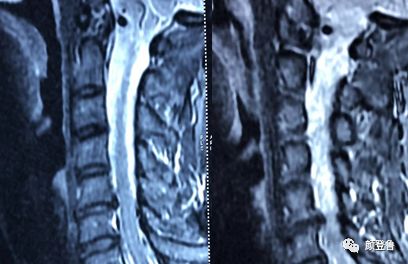

腰椎间盘突出症 (lumbar disc herniation, LDH) 是临床常见病和多发病,严重危害病人身心健康。 一旦纤维环发生破裂,那么髓核就会脱离原有位置,形成突出,当突出压迫神经产生临床症状时,才称之为腰椎间盘突出症。 、颈椎病、开放术后复发的腰椎间盘颈椎间盘突出症的病例分享 颈椎间盘突出症的发病 原因 是 指 在椎间盘发生退行性变的基础上,受到一定的外力作用后使纤维环和后纵韧带破裂,髓核突出而引起颈髓或神经根受压 。 主要的症状表现为: 单侧上肢或手部剧烈疼痛或麻木 、 步态不稳 、 颈部不适 等临床症状。May 27, · 1、虽然颈椎MRI检查明确有:颈4/5、5/6椎间盘膨出,并向右旁中央型突出相应的硬膜囊,但没有颈椎间盘突出引起的神经根损害的症状,如手麻痛、下肢乏力、走路踩棉花感以及脊髓压迫等的症状。 2、根据临床的三步定位诊断 (1)症状:反复颈部不适,偶有酸痛,伴头晕,颈部僵硬感半年。 (2)体查:C2/3/4右后关节压痛,C4/5左后关节压痛,后枕部肌群紧,双侧斜方肌